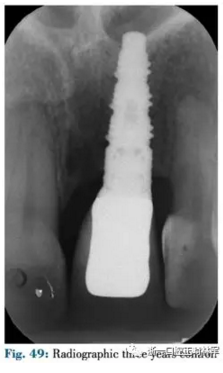

4月后在最終修復(fù)前使用臨時(shí)冠擠壓齦乳頭(圖48,49)。